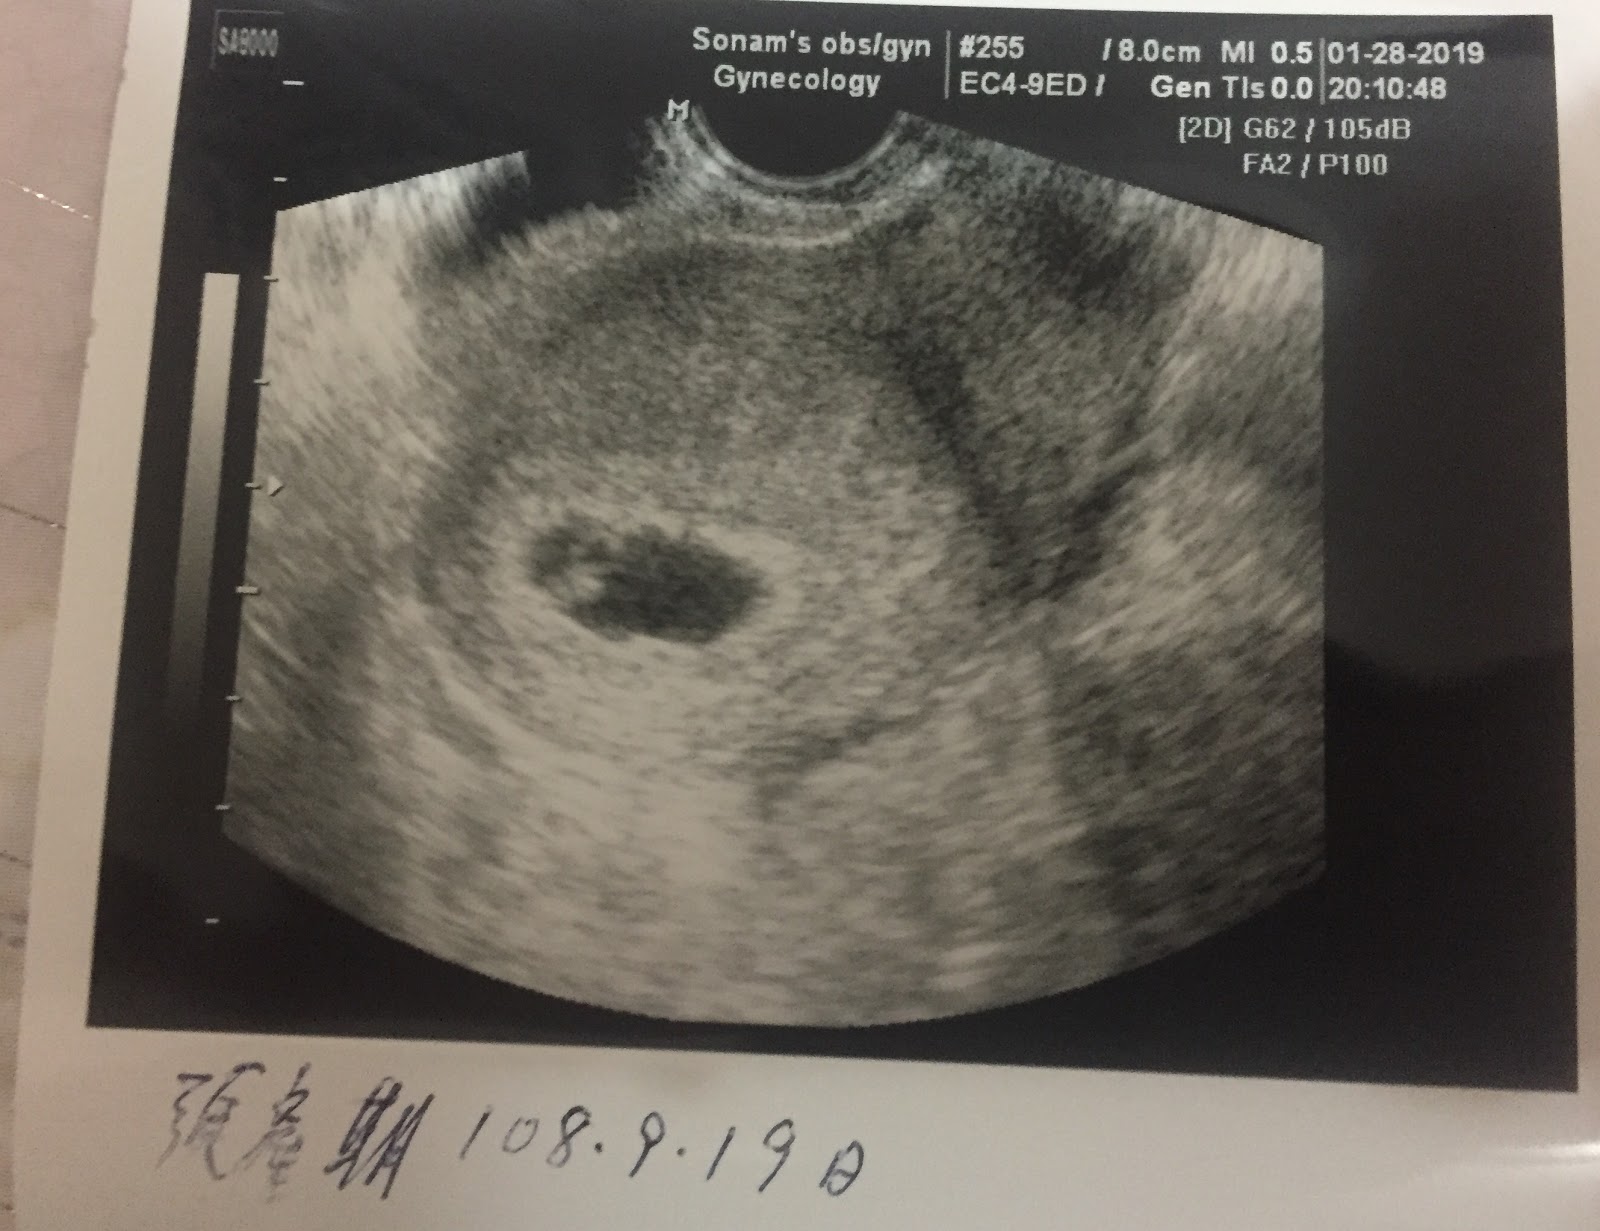

| 1月28日聽到心跳與看到卵黃囊 |

經由郭索南醫師親手寫下預產期108年9月19日,夫妻兩人也確定這不是所謂的空包彈,並且也知道未來在椪柑呱呱墜地之前,有一條辛苦漫長的路要走。當然墜地後肯定更難走。(嘆氣)